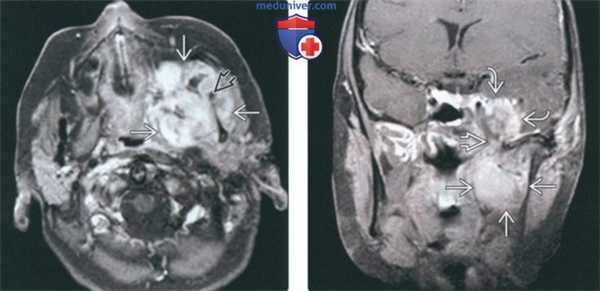

(Слева) На аксиальной КТ без КУ у пациента со шванномой ЧМН V3 визуализируется хорошо отграниченная неоднородная солидная опухоль в жевательном пространстве слева приводящая к ремоделированию крыловидных пластинок, что свидетельствует о медленном росте.

(Справа) На корональной МРТ (Т1 ВИ С+ FS) у этого же пациента визуализируется шваннома жевательного пространства неравномерно накапливающая контраст, с минимально выраженным распространением в полость черепа через расширенное овальное отверстие.

(Слева) КТ без КУ, аксиальная проекция. У пациента с шванномой нижнечелюстного нерва в левом жевательном пространстве обнаружена гетерогенная солидная опухоль с четкими контурами, которая ремоделирует пластинки крыловидного отростка. Такие находки характерны для медленнорастущей опухоли.

(Справа) МРТ Т1ВИ FS c КУ, коронарная проекция, этот же пациент. Шваннома жевательного пространства, которая неравномерно накапливает контрастное вещество. Имеются признаки минимального распространения опухоли в полость черепа через овальное отверстие. (Слева) КТ в костном окне, аксиальная проекция. У пациента установлен диагноз нейрофиброматоза 2 типа. Правое овальное отверстие расширено, в то время как размеры левого овального отверстия находятся в пределах нормы. Подобное расширение отверстий черепа без разрушения кортикального слоя характерно для доброкачественных опухолей нервной оболочки.

(Справа) МРТ Т1ВИ FS c КУ, коронарная проекция, этот же пациент. Шваннома жевательного пространства, которая неравномерно накапливает контрастное вещество. Имеются признаки минимального распространения опухоли в полость черепа через овальное отверстие.